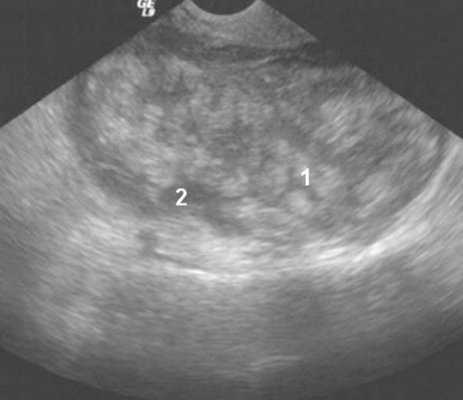

Метастазы опухолей верхних отделов пищеварительного тракта, желчного пузыря, желчных протоков и поджелудочной железы

Метастазы первичного рака желчного пузыря, желчных протоков и поджелудочной железы визуализируются как многокамерные-солидные образования с многочисленными мелкими разного размера камерами без некроза. Опухоли были различной эхогенности с гиперэхогенными перегородками, с изоэхогенным или гиперэхогенным твердым компонентом. Опухоли и перегородки были гиперваскуляризованы (Рис.3).

Рис.3. Метастазы опухолей верхних отделов пищеварительного тракта (желчного пузыря, желчных протоков, поджелудочной железы): многокамерная-солидная опухоль с небольшими камерами (1) и с твердым компонентом (2).